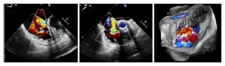

手术在患者全麻状态下进行,经股静脉入路,在经食道超声心动图和X射线引导下将DragonFly-T™瓣膜夹器械输送到右心室,捕捉和钳夹三尖瓣前叶和隔叶并关闭瓣膜夹,利用经食道超声心动图反复确认手术效果后,zui终释放三尖瓣瓣膜夹,术中共植入3枚瓣膜夹,瓣膜夹位置和功能良好,三尖瓣反流分级由术前的5+(图2)降至术后即刻的1+(图3),肝静脉血流明显改善(图4),手术顺利完成。

图2.术前经食道彩色多普勒超声图

图3. 术后经食道彩色多普勒超声图